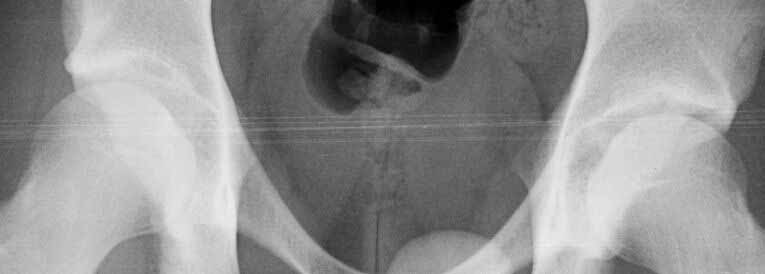

I believe this patient has anterior hip impingement caused by a retroverted acetabulum. This is seen on the submitted AP x-ray by observing the overlap of the anterior wall and posterior wall. In an acetabulum with "normal" version, the anterior wall shadow meets the posterior wall shadow at the superio- lateral aspect of the acetabulum, and they do not overlap as you follow the lines inferiorly. In an acetabulum with retroversion, the two shadows cross over the femoral head, making a figure 8 pattern.

To further confirm this, obtain a full AP pelvis film and a false profile view of both hips. In addition, the patient has an element of hip dysplasia, seen by his decreased center edge angle. On physical exam, his pain will be reproduced by hip flexion, adduction and internal rotation, when the anterior surface of the femoral neck impinges on the anterior labrum and wall. An MRI may show hypertrophic changes in the femoral neck. I also recommend a gadolinium MRI hip arthrogram to ensure there is no significant labral pathology.